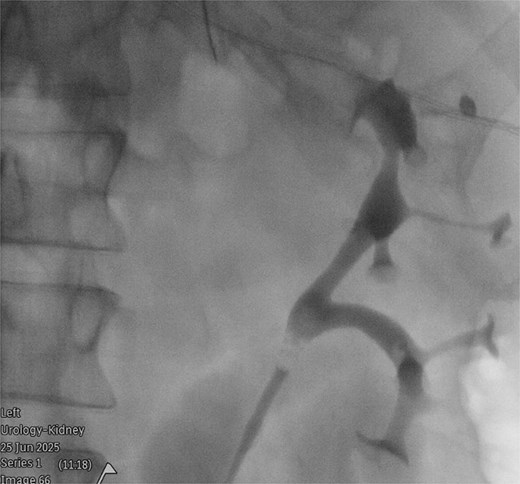

A 54-year-old man (Mr MP) presented to the colorectal clinic with recurrent sigmoid diverticulitis, on a background of Crohn’s disease, renal cell carcinoma (managed with right nephrectomy), and obesity (body mass index 32). A laparoscopic anterior resection was performed to remove the most affected segment of bowel. Surgery was difficult due to dense adhesions from diverticulitis, previous surgery, and the patient’s obesity. Despite over an hour of careful dissection, attempts to visualize the left ureter were unsuccessful, and a retrograde urethrogram under fluoroscopic guidance was required. This demonstrated a partially duplicated collecting system, with two renal pelvices converging into a single intact ureter which entered the bladder at a single ureteric orifice (Fig. 1). A ureteric stent was placed, however the left ureter still could not be visualized. As such, the decision was made to use intraureteral ICG to assist with identification. A 25 mg vial of ICG was diluted with 10 ml of sterile water, and a total of 12.5 mg (5 ml) of ICG was injected. This was detected laparoscopically using a Storz Opal1® 4 K-NIR/ICG camera using the Overlay and Monochromatic visualization modes (Fig. 2). This method revealed two distinct tubular fluorescent structures representing duplicated ureters, which were not clearly visible on the retrograde urethrogram. Both branches of the bifid ureter were narrow in caliber, which was the reason for difficulties in its identification. With ICG, the duplicated ureter was traced to its distal lateral location and protected. There were no adverse events from ICG administration. The ureteric stent was removed immediately post-operatively. Mr. MP experienced transient mild hematuria post-stent removal. Mr. MP otherwise made an uncomplicated postoperative recovery, and was discharged at Day 5 post-procedure.

Retrograde urethrogram under fluoroscopic guidance, demonstrating a partially duplicated collecting system, with two renal pelvices converging into a single intact ureter.